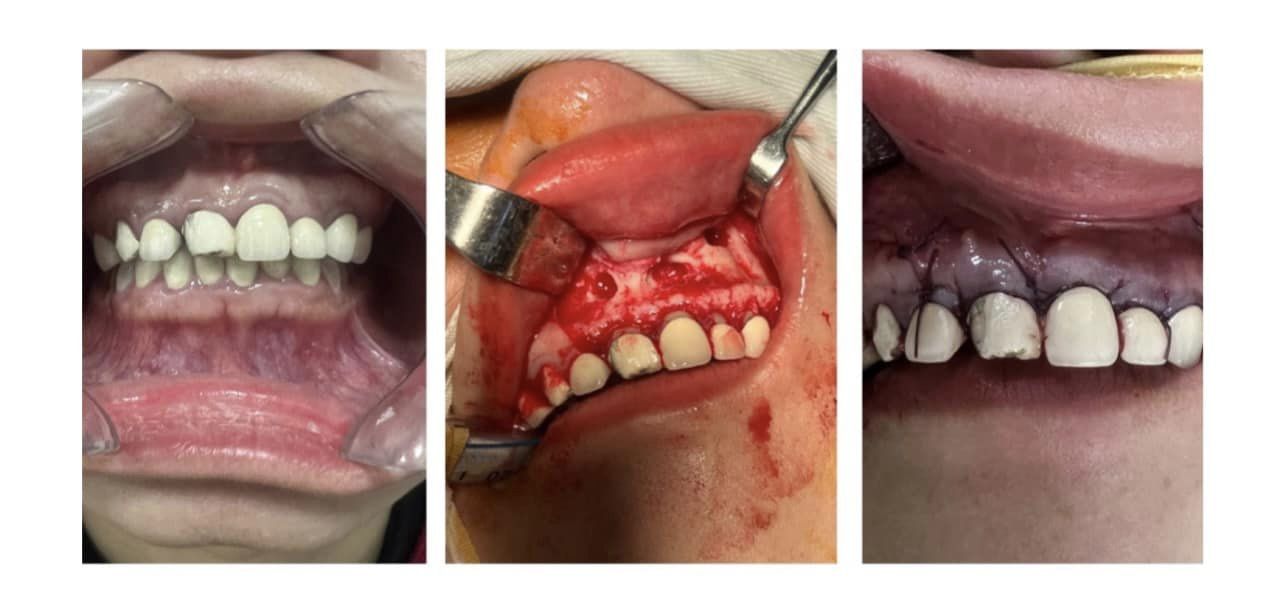

Gần đây, khoa Răng Hàm Mặt, Bệnh viện Đa khoa tỉnh Bắc Giang tiếp nhận 1 nữ bệnh nhân N.

.H (36 tuổi, địa chỉ tại Lạng Giang, Bắc Giang), đi khám do có khối sưng cục không đau, vùng răng cửa hàm trên. Sau khi được thăm khám và chukp x-quang phát hiện vùng răng cửa hàm trên có khối phồng kích thước 3x2cm, sờ căng tức, có dấu hiệu bóng nhựa, răng giả từ răng 14-24 (8 chiếc răng) .

Ngay sau khi tiếp nhận, bệnh nhân được bác sĩ tiến hành phẫu thuật cắt nang răng vùng cửa hàm trên.